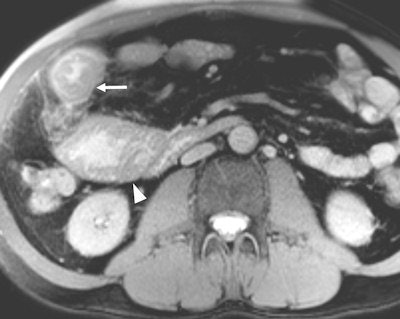

A 56-year-old patient with Crohn's disease presented with a worsening clinical condition spanning three months. Active Crohn's disease was suspected clinically. MR enterography axial fat-saturated true-FISP image demonstrates circumferential irregular small bowel wall thickening -- tumor with adjacent fat infiltration (white arrow) and prestenotic bowel dilatation (arrowhead). MRI findings demonstrated a small bowel primary tumor as a cause of the symptoms; histopathology revealed adenocarcinoma. There was no evidence of active Crohn's disease.Peritonitis, or serositis, of small bowel loops may occur in common diseases causing acute abdominal pain (e.g. appendicitis), in postsurgical patients and in rarer diseases such as familial Mediterranean fever, Kavaliauskiene wrote. This is a hereditary autosomal recessive disease with the highest prevalence in Turkey and lower prevalence in Israel, Armenia, and other Middle East countries. The fever is also found in Greece, North Africa, Italy, Germany, France, the U.S., and Japan. The prevalence of the gene associated with familial Mediterranean fever mutation in different ethnographic groups predisposes such distribution. Distribution is related to world migration as most ancient mutations appeared in the Middle East -- in the former area of Mesopotamia -- and are thought to be spread all over the world.